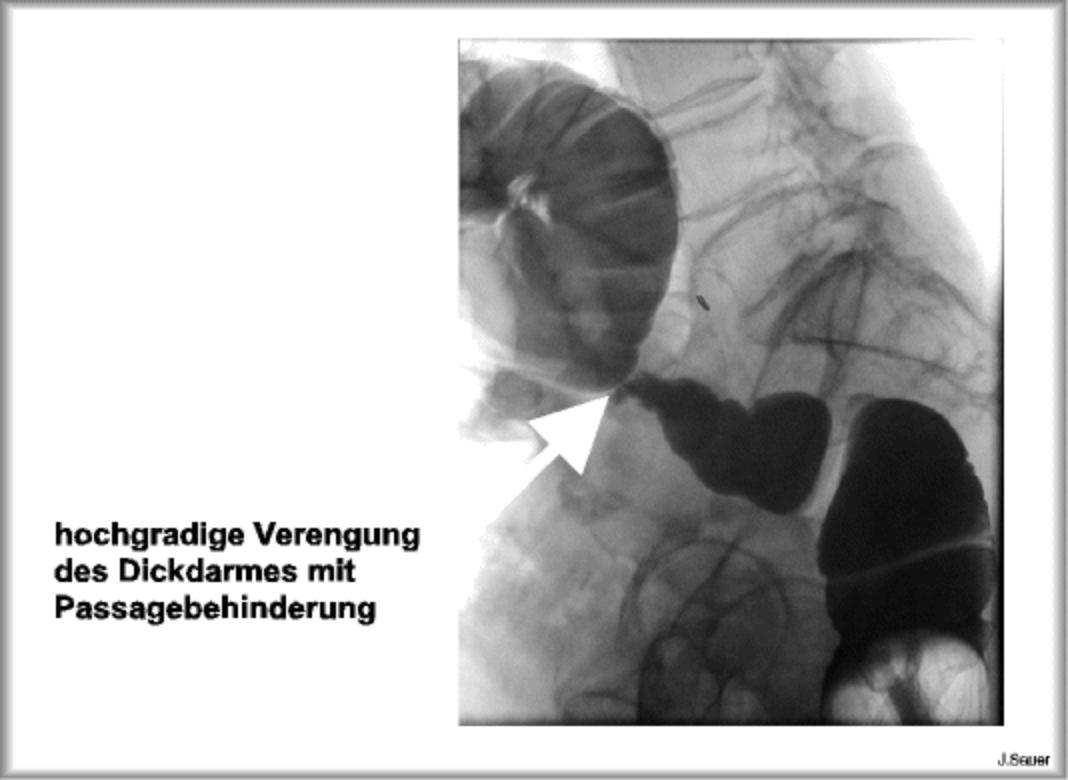

Bei der Operation eines Darmverschlusses handelt es sich um einen großen Eingriff, der unter Vollnarkose stattfindet. Nachdem die Haut ausreichend desinfiziert wurde, setzt der Chirurg einen geraden Schnitt in der Bauchmitte auf Höhe des Nabels ( mediane Laparotomie ). Die Höhe des Schnittes kann variieren und richtet sich nach der.. Bei einem Darmverschluss handelt es sich um eine Blockade, bei der Nahrung, Flüssigkeiten, Verdauungssekrete und Gase überhaupt nicht mehr oder nur bedingt weiterbefördert werden. Die häufigsten Ursachen bei Erwachsenen sind Narbengewebe nach einer früheren Bauchoperation, Hernien und Tumore. Schmerzen, Aufblähung und Appetitverlust.